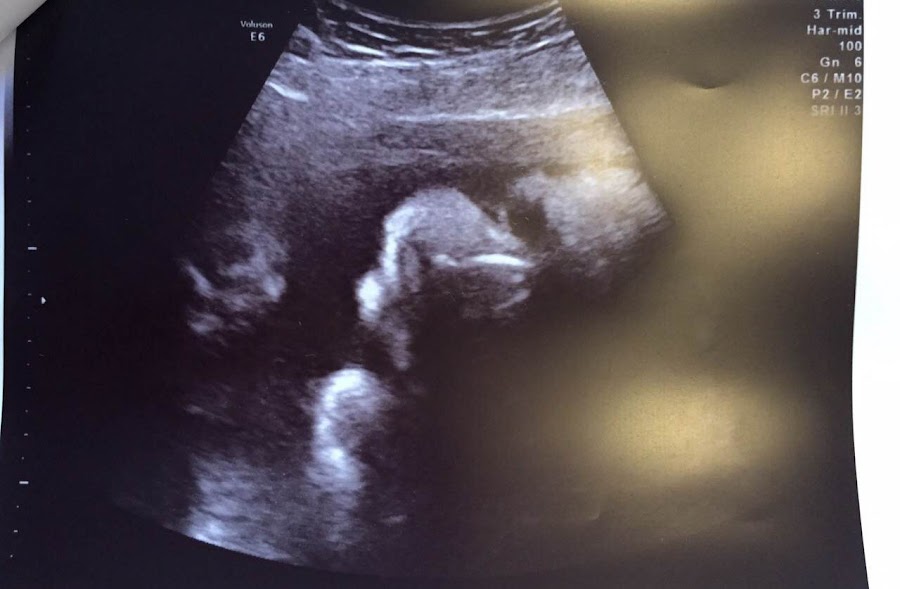

Ayer estuvimos en la gine, tocaba ecografia!!! El niño está perfecto, muy gordito... Pero las gines, viendo el tamaño del padre, me dijeron que era muy normal!!!!